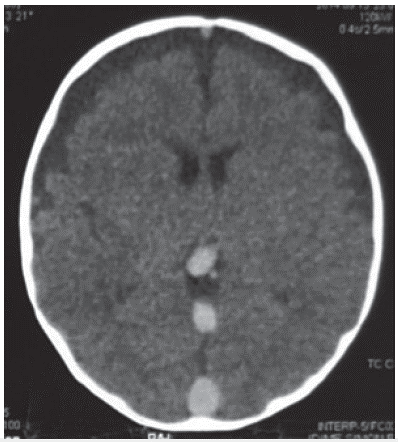

Se realizó un electroencefalograma en el que no se observaron descargas epileptiformes y una tomografia axial computarizada cerebral en la que se evidenció una trombosis de todos los senos venosos cerebrales (figura 1).

Tomografia axial computarizada cerebral en la que se evidenció una trombosis de todos los senos venosos cerebrales.

Figura 1: Tomografia axial computarizada cerebral en la que se evidenció una trombosis de todos los senos venosos cerebrales.

Fuente: autora.